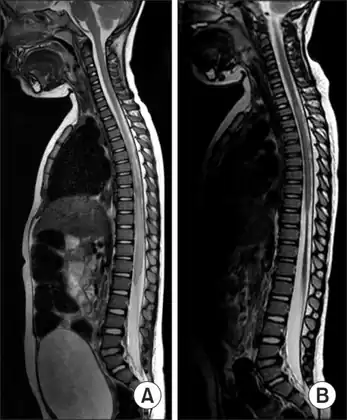

MRI of individual diagnosed with transverse myelitis

Axial T2 MRI of cervical spine demonstrating normal cord signal (green circle) and increased T2 signal in the central cord (red circle).